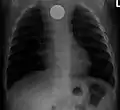

سکه ای که در AP CXR در مری دیده میشود

سکه ای که در CXR جانبی در مری دیده میشود